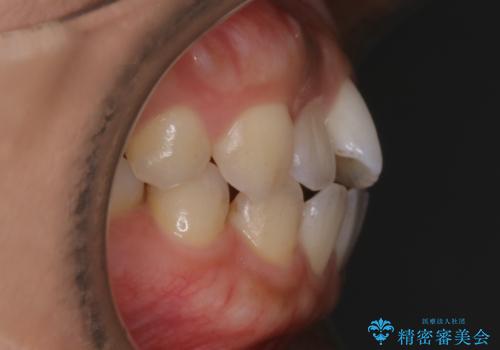

- 矯正治療を主訴にご来院されました。

すきっ歯と噛み合わせの治療をしたいとのことで、インビザラインを用いて矯正治療を行うこととなりました。

すきっ歯の場合、ガタつきを治したりするのに必要なスペースが最初から空いているため、そのスペースを利用して比較的短期間で効率よく治療を進めることが可能となります。

初診時の写真では一見噛み合わせには問題がないように見えても、実際に精密な検査を行うと改善すべき点が見つかる場合も多くあります。